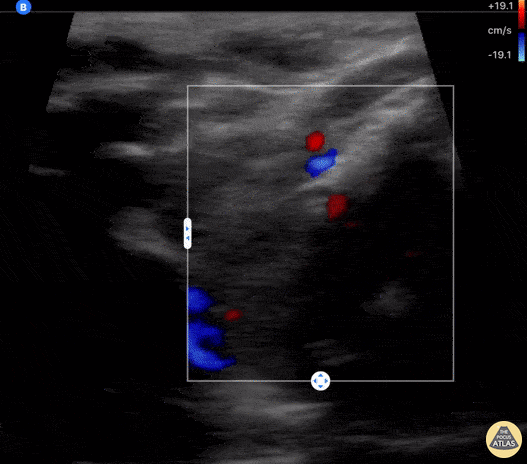

An 18-year-old female with 2 week hx COVID presented to an outpatient clinic where labs included a TSH <0.01 and Free T4 6.75. She was sent to ED for further evaluation of tachycardia (HR 130 bpm). ED evaluation included POCUS that was notable for bilateral thyroid lobe enlargement without nodules, findings consistent with COVID-induced thyroiditis. Paul Khalil, PEM POCUS Fellow at Denver Health/University of Colorado @Khalil3Paul